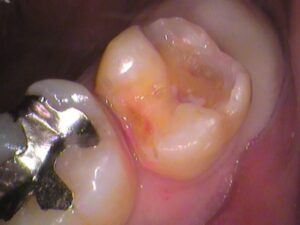

一か所気になる所が。

ココですね。

歯の外側なのですが、黒く虫歯の存在があります。

残してしまって、あとでここから虫歯が進行してしまっては困ります。

虫歯は取り除き、

歯の薄くなってしまっている所も整え、

セラミックが入るように形を整えました。

患者さんのご希望も考慮し、

なるべく最小限の範囲で治療を済ませます。

セラミックがセットされました。

歯の色が綺麗に仕上がっています。

治療した所が分からないですね。

最初の状態と見比べてみると、

はやり歯は白い方がいいですね(^^)/